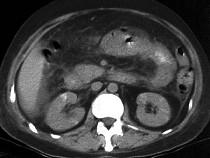

问题 男,32岁,阵发性腹痛、腹胀,伴恶心、呕吐,腹部可触及包块,影像检查如图,最佳的诊断是什么 ( )

选项 A.小肠肿瘤 B.麻痹性肠梗阻 C.空肠套叠 D.回肠套叠 E.结肠套叠

答案 C